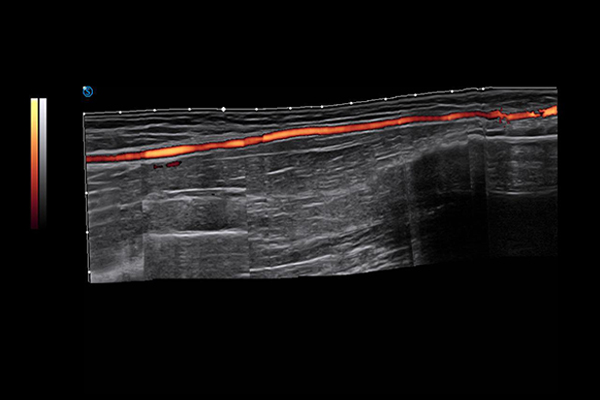

VS Flow is highly sensitive to low velocity blood flow signal and especially suitable for superficial blood flow examination

Panoscope displays image information for extensive tissue, offering abundant information of the relationship between the lesion and surrounding tissues.